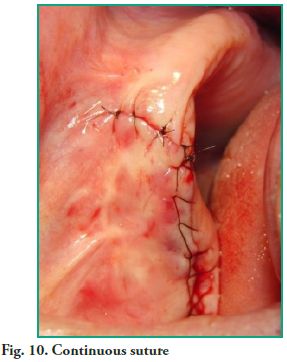

An ostectomy was performed using a rotary instrument and copious irrigation with normal saline is applied to enlarge the fenestration in order to improve visibility. The lesion was fully removed with sinus lift curettes using the enucleation and curettage technique, and the exeresis of the bone septum that divided the lesion was performed afterwards (Figs. 7, 8 and 9). Finally, closure was performed using continuous suture with 5-0 nylon thread (Fig. 10).

An ostectomy was performed using a rotary instrument and copious irrigation with normal saline is applied to enlarge the fenestration in order to improve visibility. The lesion was fully removed with sinus lift curettes using the enucleation and curettage technique, and the exeresis of the bone septum that divided the lesion was performed afterwards (Figs. 7, 8 and 9). Finally, closure was performed using continuous suture with 5-0 nylon thread (Fig. 10).